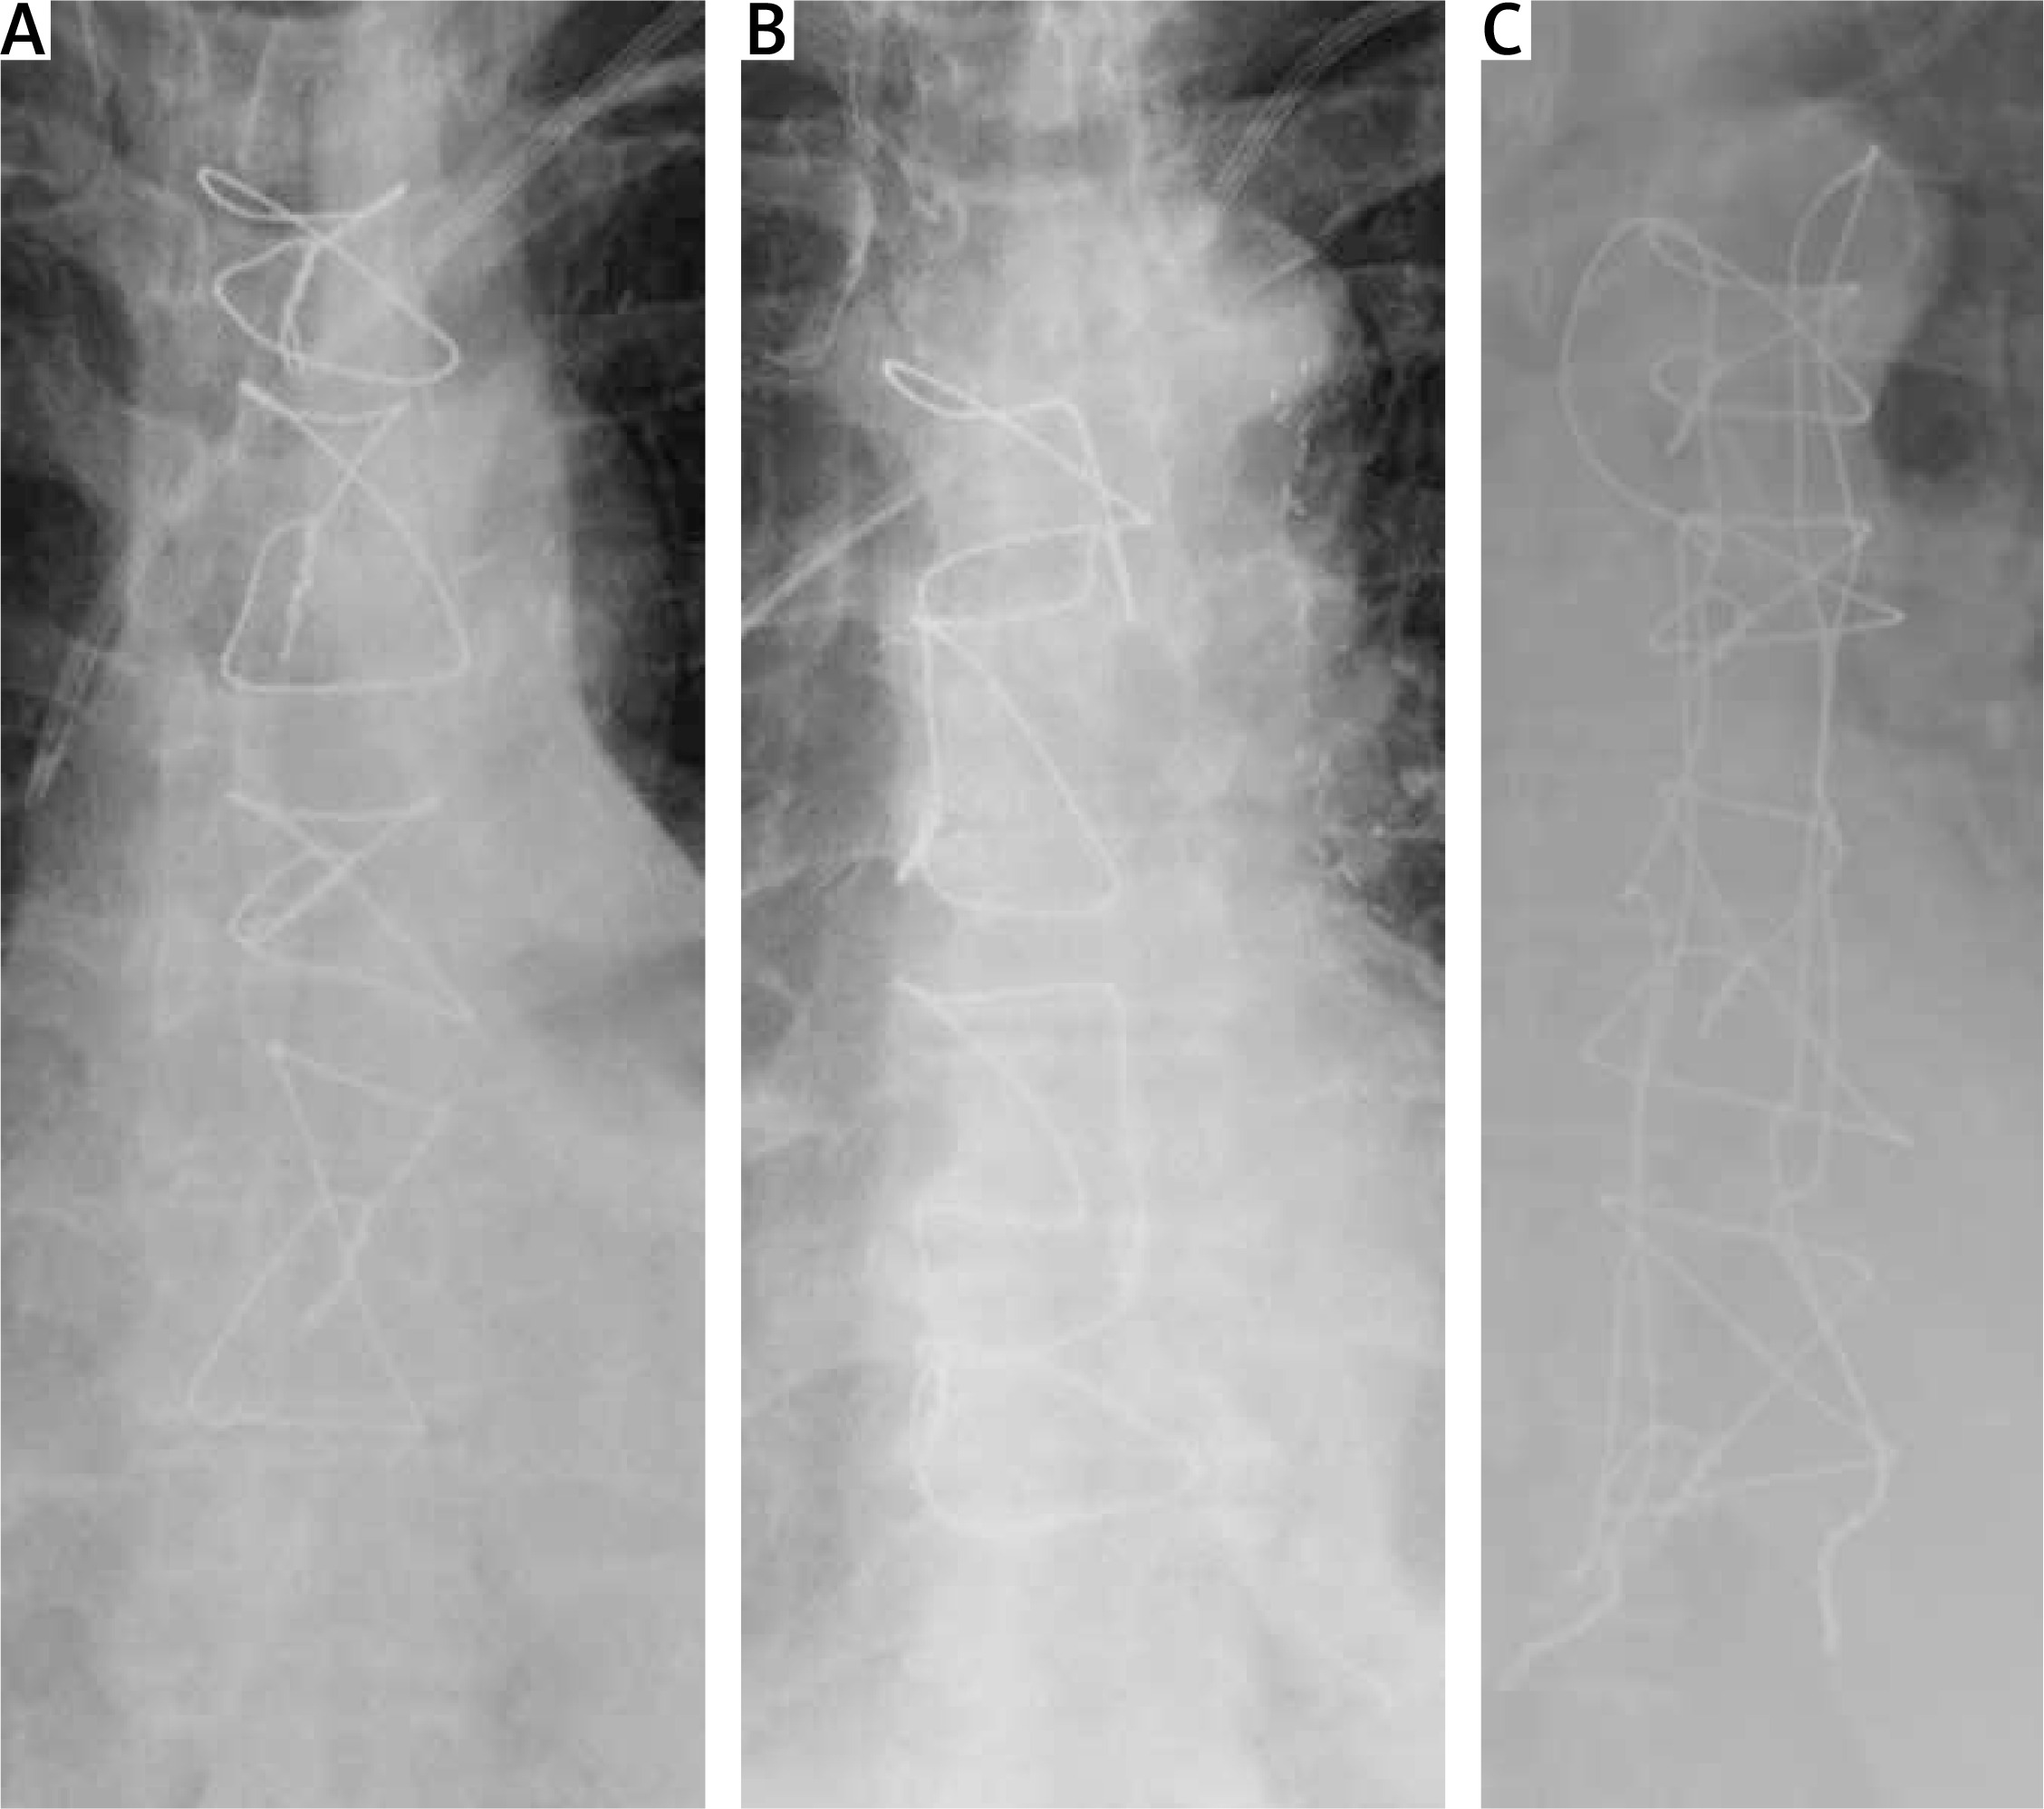

In the defined method, the sternum is closed with standard 5 mm/45 cm surgical stainless steel sternal wires (Doğsan, Trabzon/Turkey) as in the “figure of 8”. However, the wires are knotted laterally with the corresponding previous one sequentially on the lateral side of the sternum rather than midline knotting as in the “figure of 8” (Figures 1 A–C, 2 A, B). The name comes from the surgical view of wires when the sternum is closed. The wires are in the form of “/” (Figure 3).

Figure 1

Schematic wiring order: A – sternal wires are applied in order from a to d, B – in “figure of 8” wiring “a”s are knotted with “d”s, C – in “/” wiring, each “a” is knotted with the next “a”, and each “d” is knotted with the next “d”

Robicsek weave is performed as defined originally by the author [3] (Figure 2 C).